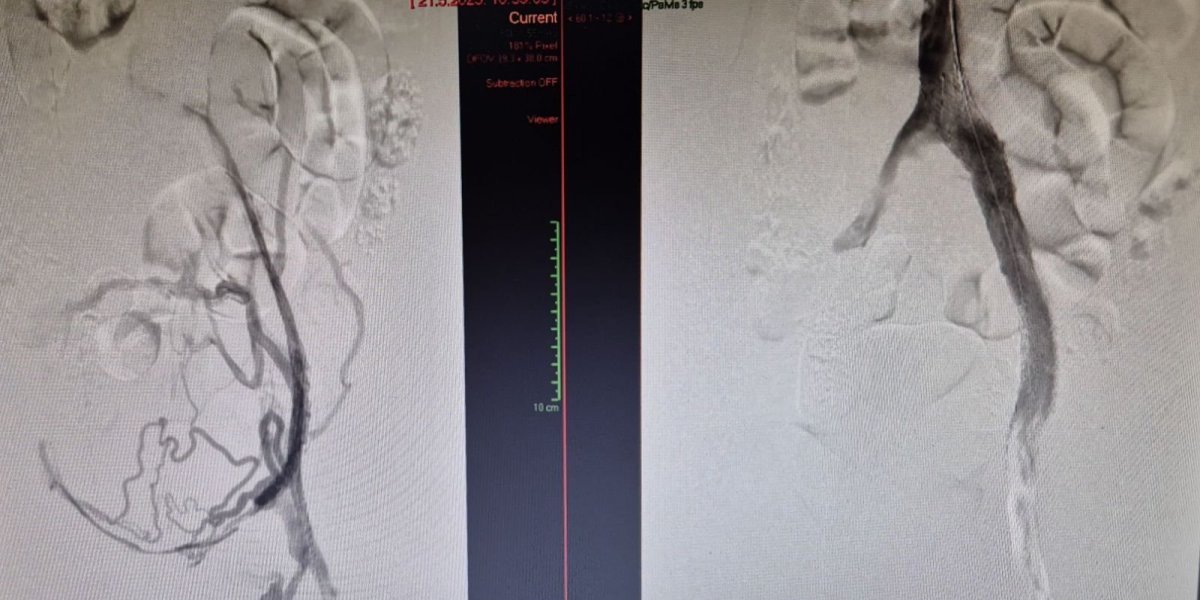

Na Odeljenju za interventnu radiologiju Univerzitetskog kliničkog centra Vojvodine (UKCV) uspešno je izvedena prva endovaskularna intervencija na bedrenim venama u Srbiji.

Ova inovativna procedura sprovedena je kod pacijentkinje (24) sa okluzijom bedrenih vena, izazvanom hroničnom trombozom dubokih vena. Tokom intervencije, plasiran je specijalni venski stent.

Zahvat su izveli interventni radiolozi dr Slobodan Torbica i dr Andrej Petreš, uz stručno proktorstvo prof. dr Suata Doğancija iz Turske, jednog od vodećih evropskih stručnjaka u oblasti venske patologije.

"Uvođenje ove procedure u kliničku praksu UKCV-a predstavlja značajan iskorak u tretmanu hroničnih venskih oboljenja, jer po prvi put pacijentima u Srbiji omogućava primenu savremenog, minimalno invazivnog terapijskog pristupa koji je do sada bio nedostupan u domaćem zdravstvenom sistemu", kažu u KC Vojvodina.